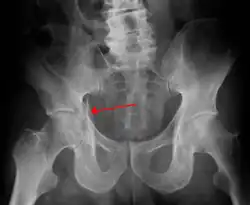

1. Pelvis with both hips antero posterior view. This view shows six important landmarks of the acetabulum, specifically:

• Pelvic brim

• Ilio ischial line

• Tear drop

• Anterior wall

• Posterior wall

• Weight bearing dome